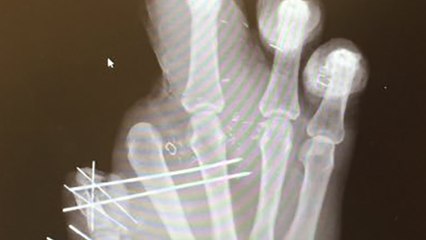

New York Giants defensive end Jason Pierre-Paul is still trying to prove that he can play even without a finger or two! The first image of Pierre-Paul’s injured hand from his Fourth of July fireworks accident was revealed and just 24 hours after the two-time Pro Bowler posted a video of one his workouts. Now Pierre-Paul is responding to critics again by posting another video of a bench-press workout. There’s a towel covering his hand, but he seems to have no problem lifting the bar nonetheless.